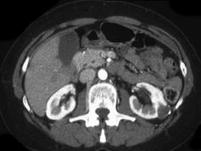

问题 女,24岁,请根据所示图像,选择最可能诊断 ( )

选项 A、左侧囊性肾癌 B、左侧肾盂旁囊肿 C、左侧钙化性肾囊肿 D、左侧肾包虫囊肿 E、左侧单纯性肾囊肿

答案 C